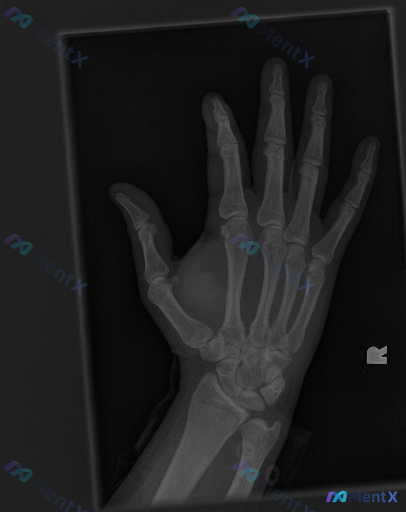

整理到一个临床与影像结合的手部病例资料,想和大家讨论一下思路: --- 影像资料:右侧手部正位X光片 影像学观察: - 骨骼:各掌骨、指骨、腕骨骨皮质连续,未见明确骨折线、成角或阶梯状改变;骨小梁排列规律,未见局部密度异常减低或硬化区;第一掌骨基底部、第五掌骨颈等特定部位也未见典型骨折表现。 - 关...